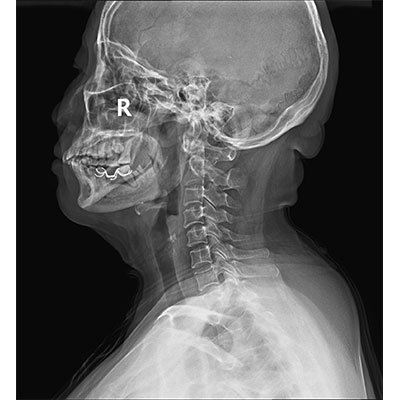

● 采用自主研發(fā)的技術(shù),在保證優(yōu)質(zhì)圖像的前提下,大大降低X射線劑量,用心呵護醫(yī)護工作者及患者的健康。

● 短曝光時間,便于老年人、兒童、殘疾人進行臨床拍攝。避免這類群體因不能有效控制身體運動等因素造成的運動偽影,提高攝片質(zhì)量及效率。